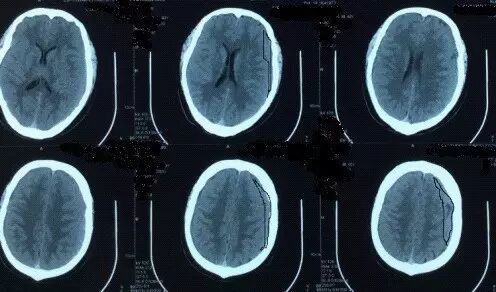

2017年5月7日上海某医院头颅CT提示:颅脑术后,双侧额颞顶部硬膜下积液积血(图4)。于2017年5月9日行双侧钻孔引流术,2017年5月12日头颅CT提示:钻孔术后改变,颅内积气(图5)。患者术后头痛症状持续加重,出现意识不清,5月15日再次复查头颅CT提示脑肿胀明显(图6),于5月17日再次行右侧硬膜下血肿清除+左侧硬膜下血肿钻孔引流术,术后患者出现脑疝,于2017年5月21日行右侧额颞顶扩大去骨瓣减压术+血肿清除术。(图7)

图7. 2017年5月22日外院头颅CT提示:右侧额颞顶部去骨瓣术后改变。

图8. 2017年7月4日本院头颅CT提示:右侧额颞顶部去骨瓣术后改变,脑室扩张。